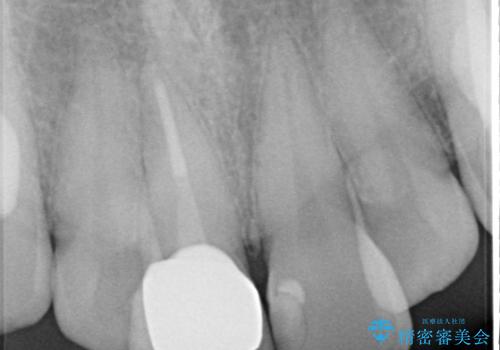

- 前歯の色が変色してきたことを主訴に来院されました。

根管治療から被せものまで治療を行いました。